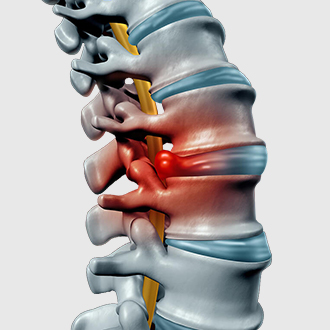

xem chi tiếtThoát vị đĩa đệm

Thoát vị đĩa đệm là bệnh lý xảy ra khi nhân nhầy của đệm cột sống chệch ra khỏi vị trí bình thường, xuyên qua dây chằng và chèn ép vào cột sống hoặc các dây thần kinh, gây đau nhức tê bì cột sống. Hai vị trí thường